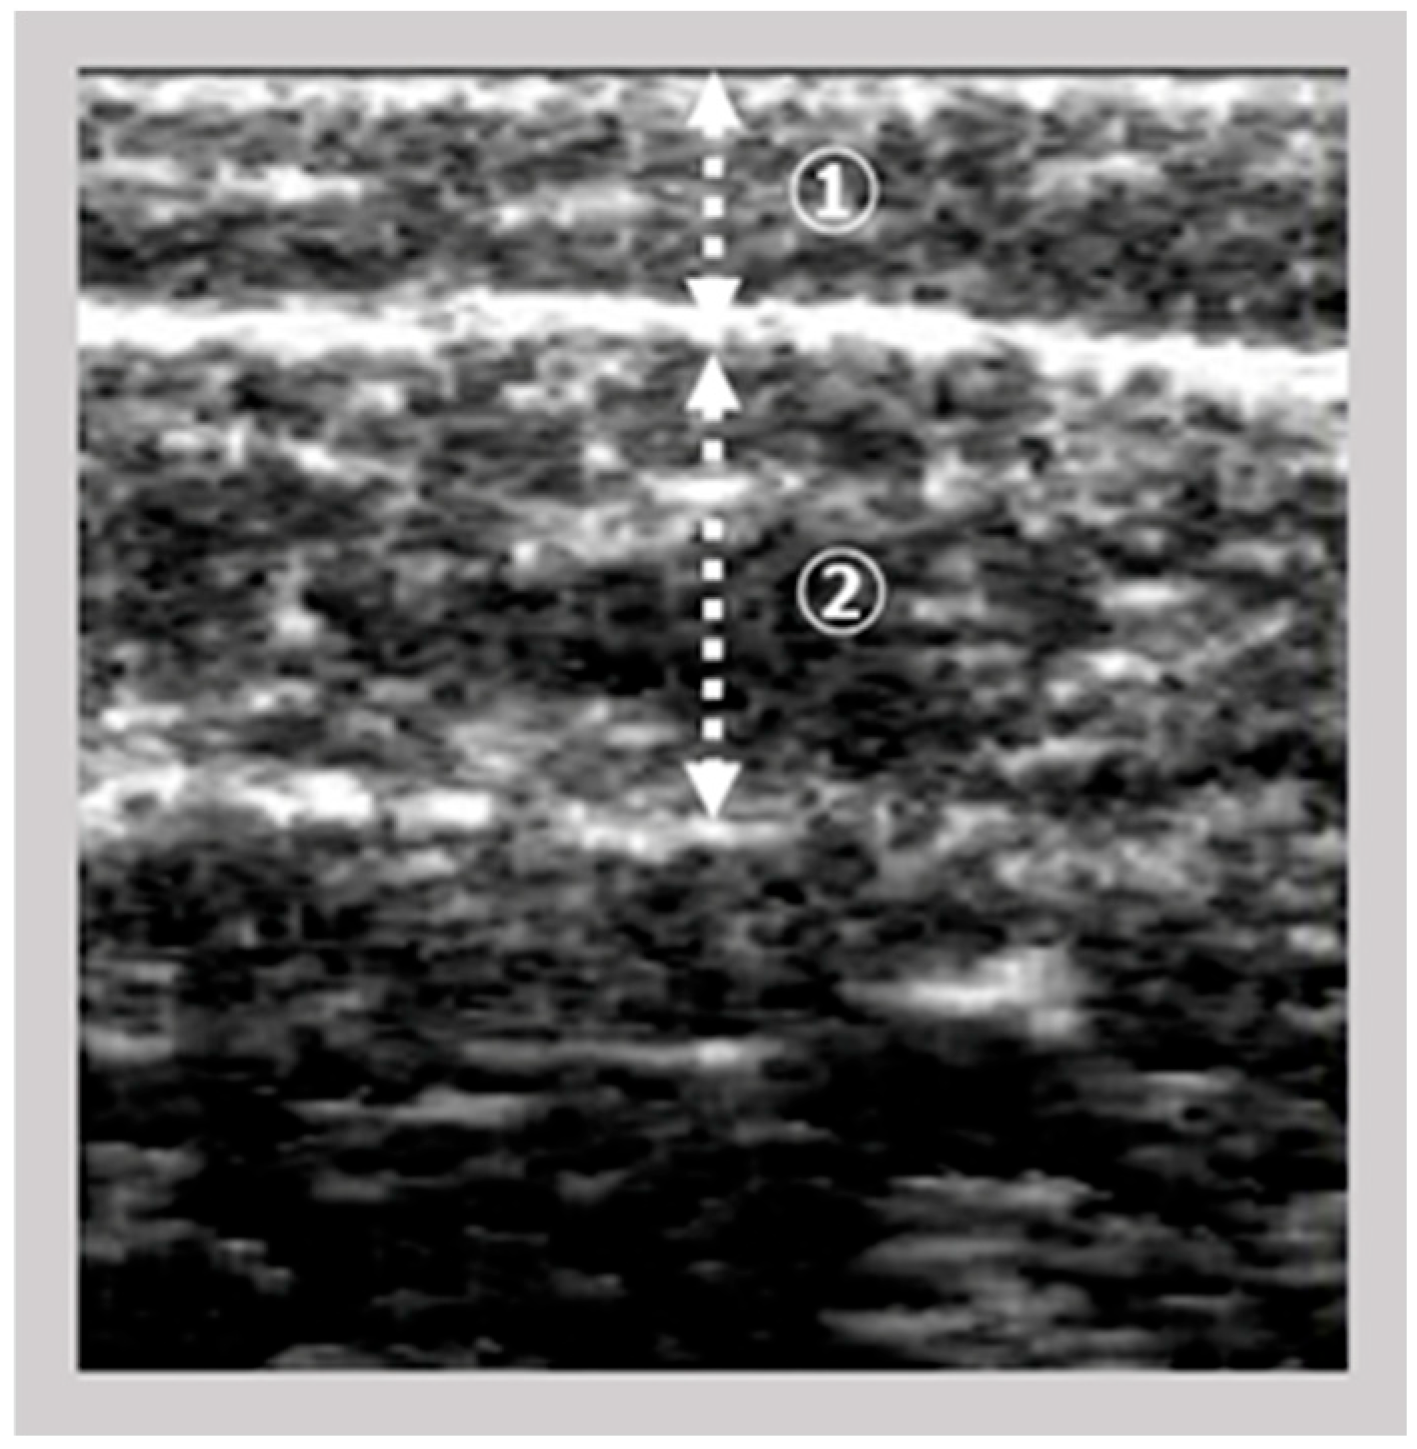

The images of the gastrocnemius muscle were obtained using an ultrasound device (View’s i; SAKAI Medical Science Co., Ltd., Tokyo, Japan) equipped with a 6-MHz linear array probe. In all patients, ultrasonography measurements were performed under fixed settings, including B-mode, a fixed dB dynamic range, fixed gain, and fixed depth of focus, which were preconfigured for skeletal muscle imaging and intentionally made non-modifiable by the manufacturer. The mode settings are not disclosed due to the device’s patent protection. The participants were assessed in a seated position with both knees flexed at 90° and the ankles at 0°. The examiner vertically and gently positioned the probe on the right medial gastrocnemius at the point of maximum below-knee circumference. The A-mode display on the device was monitored simultaneously. The examiner captured images of the subcutaneous adipose tissue and gastrocnemius muscle (Figure 1). The subcutaneous fat thickness (SFT) was defined as the distance between the skin surface and the upper fascia of the gastrocnemius. Meanwhile, the GT was defined as the distance between the subcutaneous fascia and the deep fascia. A previous study investigated the intra-rater reliability of GT measurements in healthy adults when the probe pressure was maintained below 100 gf [9] reported decreased reliability under this condition. Based on these results, we set the probe pressure at 200 gf in this study to minimize measurement error.

Ultrasound images were exported as Joint Photographic Experts Group (JPEG) files, and the EI of the gastrocnemius muscle was calculated using Adobe Photoshop Elements (Adobe Systems, Inc., San Jose, CA, USA). The target area was selected to include as much muscle tissue as possible while avoiding the surrounding fascia. The selected area was converted to an 8-bit grayscale image, with the mean image brightness presented as a value ranging from 0 (black) to 255 (white) (Figure 2). The EI was calculated as the mean image brightness [10]. This study analyzed the EI and GT of the leg with the lower ABI.

Figure 2. Calculation of echo intensity from the ultrasonographic image.